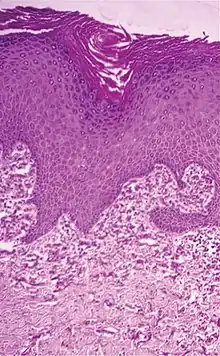

| Histopathology of perforating calcific elastosis: Clumping of short elastic fibers in the dermis.[2] | |

Perforating calcific elastosis is an acquired, localized cutaneous disorder, most frequently found in obese, multiparous, middle-aged women, characterized by lax, well-circumscribed, reticulated or cobble-stoned plaques occurring in the periumbilical region with keratotic surface papules.[3]